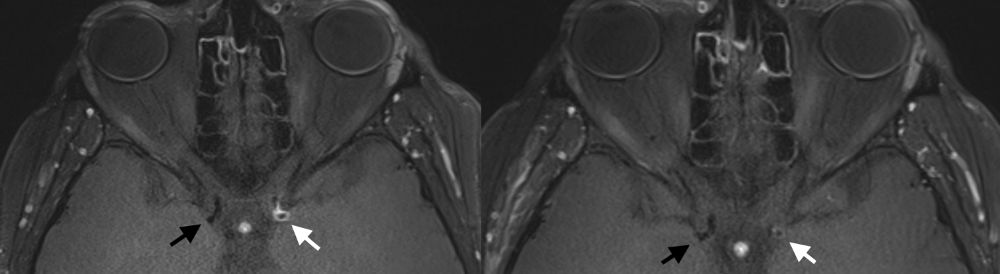

MRT Aufnahme Gefäßwand der Halsschlagader

Hochauflösende MRT Aufnahme mit kräftiger Kontrastmittelaufnahme der Gefäßwand der Halsschlagader (weißer Pfeil), welche im Verlauf von wenigen Monaten deutlich abnimmt (Bild rechts ). Die Halsschlagader der Gegenseite (schwarzer Pfeil) zeigt jeweils keine Aktivität der Erkrankung.